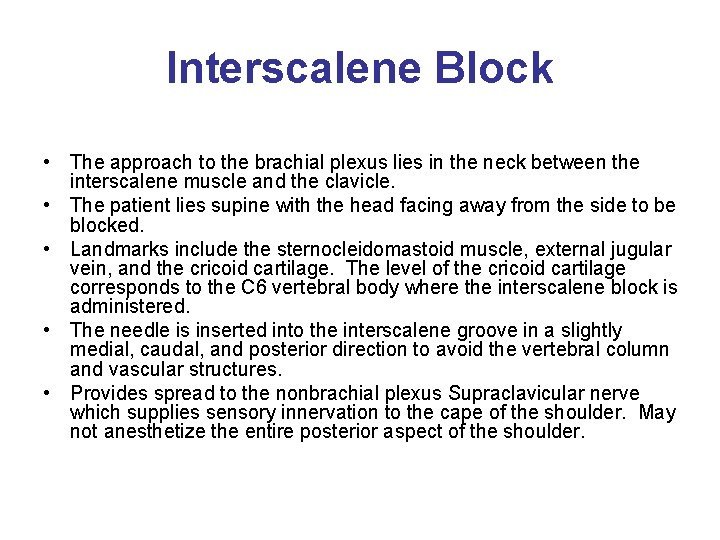

Interscalene Block • The approach to the brachial plexus lies in the neck between the interscalene muscle and the clavicle. • The patient lies supine with the head facing away from the side to be blocked. • Landmarks include the sternocleidomastoid muscle, external jugular vein, and the cricoid cartilage. The level of the cricoid cartilage corresponds to the C 6 vertebral body where the interscalene block is administered. • The needle is inserted into the interscalene groove in a slightly medial, caudal, and posterior direction to avoid the vertebral column and vascular structures. • Provides spread to the nonbrachial plexus Supraclavicular nerve which supplies sensory innervation to the cape of the shoulder. May not anesthetize the entire posterior aspect of the shoulder.

Interscalene landmarks